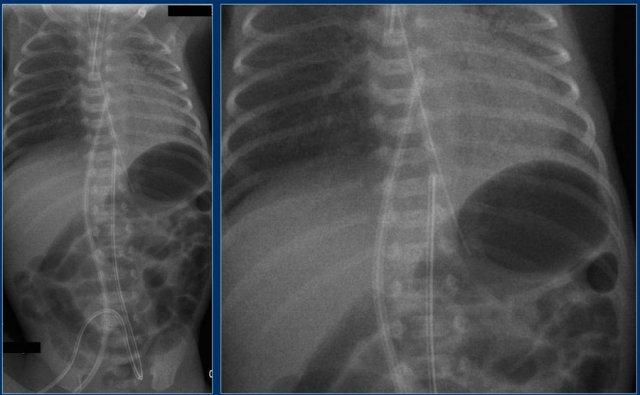

Đường truyền tĩnh mạch rốn (7

)

Quan sát hình ảnh.

Sau đó tiếp tục đọc.

Các phát hiện bao gồm:

- Đường truyền tĩnh mạch rốn quá sâu.

Đường truyền có thể đã đi qua lỗ bầu dục thông, qua nhĩ trái và vào tĩnh mạch phổi.